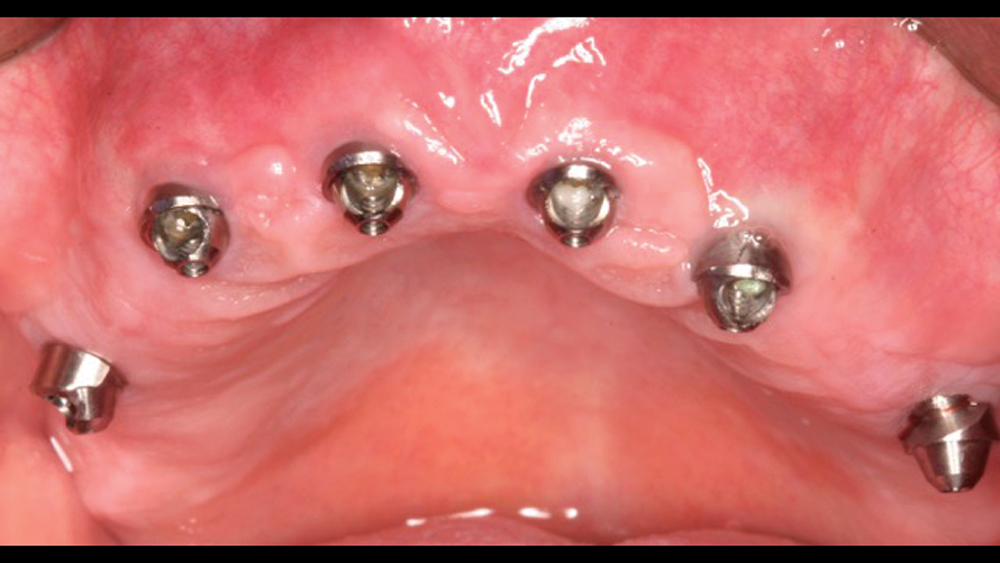

Patients who present with terminal dentition commonly suffer from discomfort, poor dental function and low self-esteem as a result of their condition. Immediate implant placement is a treatment option that offers instant, life-changing benefits for these patients while setting the stage for a predictable long-term outcome. In the presence of sufficient bone quality and volume, after atraumatically extracting the patient’s teeth, implants can be placed and a temporary appliance delivered, allowing the patient to walk out of the office with dramatically improved form and function in one appointment. This immediately enhances the patient’s quality of life and provides a significant “wow” factor for your practice.

To establish the foundation needed for a screw-retained restoration and avoid fracturing the facial plate, clinicians must position the immediately placed implant against the lingual or palatal wall of the extraction socket. This is one of the reasons I designed the Hahn™ Tapered Implant (Glidewell Direct; Irvine, Calif.) with deep, sharp threads, which enable precise directional control during insertion and prevent the implant from “walking” toward the facial plate as it is threaded into place. This thread design also leads to high primary stability in all bone types, which is essential when performing the extraction with immediate implant placement procedure.1,2

The following case demonstrates how to immediately place implants in full-arch indications. By properly positioning the implants, maximizing primary stability and providing the most durable restoration possible, the short- and long-term needs of the patient are addressed in an efficient, predictable manner.